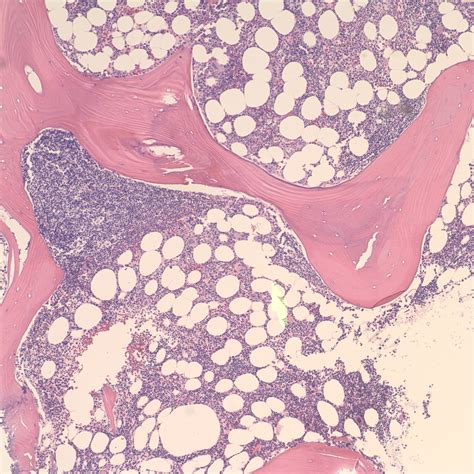

Splenic Marginal Zone Lymphoma is a B-cell neoplasm that arises from the marginal zone of the lymphoid follicles in the spleen. It is categorized as a low-grade lymphoma, meaning that the cancer cells typically multiply at a slower rate compared to aggressive lymphomas. The disease is characterized by the accumulation of small, abnormal B-lymphocytes in the spleen, leading to organ enlargement, known as splenomegaly.

To confirm the diagnosis, medical teams typically employ a combination of tests. Blood work, including a complete blood count (CBC) and peripheral blood smear, is the first step. If the suspicion of lymphoma arises, a physical examination of the abdomen is followed by imaging studies like a CT scan or ultrasound to measure the spleen's size. Ultimately, a bone marrow biopsy or, in some cases, a splenectomy (surgical removal of the spleen) provides the definitive tissue sample needed to confirm the presence of Splenic Marginal Zone Lymphoma.